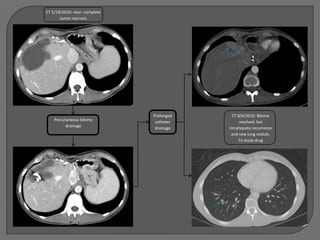

TG

39 y/o female

Fibrolamellar HCC diagnosed in 2001

Left lobe resection of 9 x 11 cm mass in 2001

Recurrence 2007 with partial right lobe

resection

CT 4/9/2010: At least

Presents with multifocal recurrence 2/2010      10 hypervascular liver

masses

Not a surgical or transplant candidate

Presented at tumor board and referred for

locoregional therapy

TACE 5/3/2010   100 mg doxorubicin on

LC beads

2 weeks later, returns

with fevers, RUQ pain

CT 5/19/2010: near- complete

tumor necrosis

Prolonged     CT 8/6/2010: Biloma

Percutaneous biloma         catheter         resolved, but

drainage              drainage   intrahepatic recurrence

and new lung nodule.

To study drug